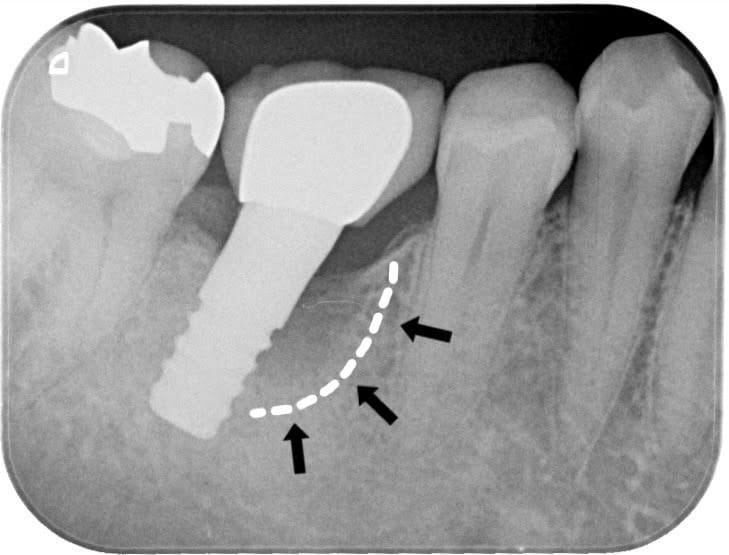

Case011 – インプラント

前医でインプラントの埋入角度が悪く、インプラント周囲炎になってしまった患者様の症例です。

インプラントが虫歯になることはありませんが、インプラント周囲炎というインプラントの歯周病にはなります。

インプラント周囲炎の主な原因は汚れ(菌)と力です。このように斜めに埋入されているインプラントは、真っ直ぐ埋入されているものに比べて汚れも溜まりやすく、噛む力も斜めにかかってしまうため、インプラント周囲炎になるリスクが大幅に高くなります。

この患者様は内側の骨が大幅に溶けてしまっていたので、前のインプラントを撤去して、骨を再生させると同時にインプラントを正しい位置と角度で埋入し直しました。溶けてしまっていた骨が治っていることもレントゲンでご確認いただけるかと思います。

インプラントは「どこの位置にどのような角度で入れるか」によって、一生使い続けられるかどうかの期待値が大きく異なります。値段だけを基準にクリニックを決めるのではなく、信用できる歯医医師と治療を進めることをお勧めします。

担当 理事長 佐藤悠野